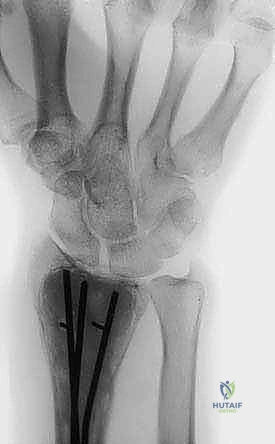

بناءً على صور الرنين المغناطيسي، يقوم الدكتور هطيف بعمل شق جراحي دقيق للوصول إلى العظم المصاب. يتم فتح نافذة صغيرة في القشرة العظمية للوصول إلى قلب الورم.

الخطوة الثانية: الكشط الجراحي الشامل (Intralesional Curettage)

باستخدام أدوات جراحية متخصصة ومناظير دقيقة (وأحياناً الميكروسكوب الجراحي)، يتم كشط وإزالة المادة الورمية المرئية بالكامل من داخل العظم. يتم غسل التجويف جيداً.

يتم إدخال مسبار التبريد أو سكب النيتروجين السائل مباشرة في التجويف العظمي. يراقب الدكتور هطيف تشكل "كرة الجليد" (Ice ball) بدقة. يتم إجراء دورات التجميد والذوبان المتعاقبة لضمان القضاء التام على أي خلايا ورمية مجهرية مختبئة في جدران العظم.

الخطوة الخامسة: إعادة البناء والترميم (Reconstruction)

بعد القضاء على الورم، يتبقى تجويف فارغ داخل العظم. يقوم الدكتور هطيف بملء هذا الفراغ إما باستخدام ترقيع عظمي (Bone Graft) أو الإسمنت العظمي (PMMA - Bone Cement). الإسمنت العظمي له فائدة مزدوجة: فهو يوفر دعماً ميكانيكياً فورياً للعظم، والحرارة الناتجة عن تصلبه توفر تأثيراً إضافياً قاتلاً للخلايا الورمية المتبقية.